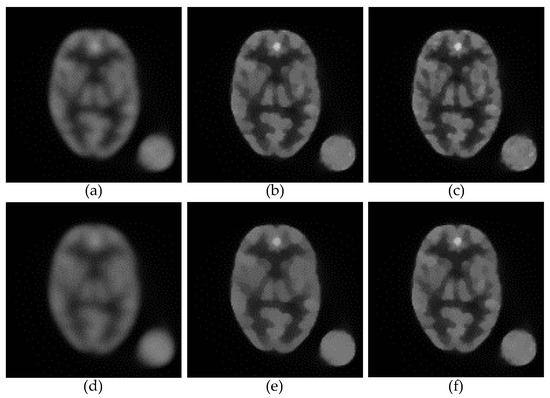

3.2. Robustness against Variation in the Smoothing Parameter